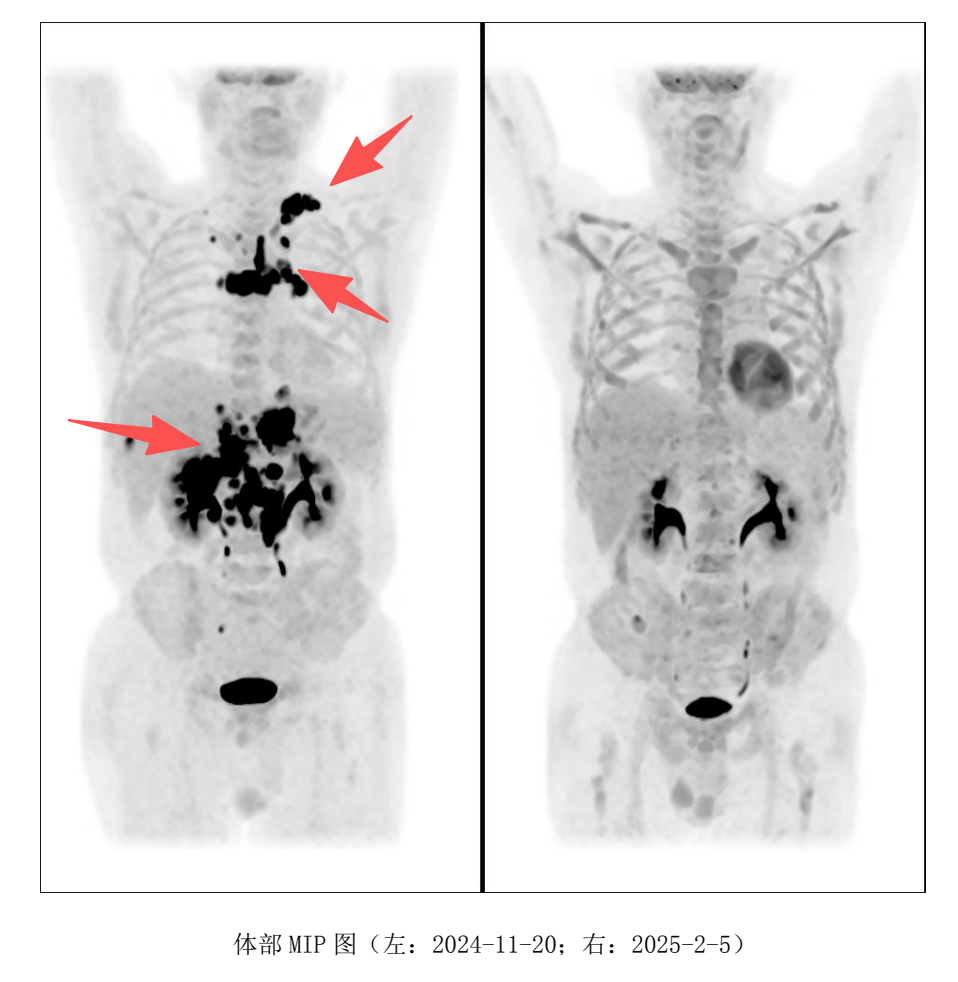

第一时间为老马联系好医生并住院后,自 2024 年 9 月起,采用Pola+Gemox方案作为CAR-T治疗前的桥接方案,FC方案进行清淋后回输CD19-CAR-T及CD22-CAR-T治疗。

双靶点CAR-T疗法被寄予厚望,然而事与愿违。回输细胞后,患者CT复查显示部分缓解,但CAR-T细胞扩增效果并不理想,且患者很快出现发热症状。11月评估时,疾病进展为PD;这样的结果对每个家庭而言都难以接受。

2025 年 2 月,PET-CT 评估显示完全缓解(CR) ,Deauville 评分为 1 分(提示无肿瘤活性),全家喜极而泣!